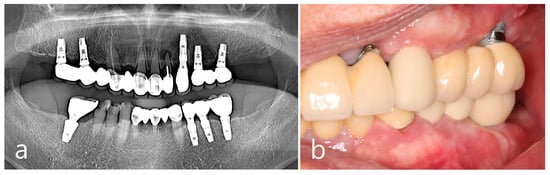

Panoramic radiography performed at the first visit showed that the implants were placed in both the posterior maxillary regions and the first molar of the left mandible. The patient reported that the implants had been loaded for 7 years. Both prostheses in the posterior maxilla were cement-type three-unit bridges and a single screw-type crown was delivered in the left posterior mandible. An assessment of the prostheses showed no specific occlusal overloads or interferences in the posterior implants. Ovoid radiopaque masses were observed in the posterior alveolar ridges where the implants were placed (Figure 1a). The proliferating mass in the maxilla showed a radiolucent medullary space within the outer cortical layer, and the mass in the mandible showed radiopacity with uniform bone density. The root rests of the left maxillary canine and right mandibular first molar were extracted and replaced with dental implants. After 1 year of prosthetic loading on the two additional implants, the panoramic view showed a more pronounced radiopaque mass in the three previous areas (Figure 1b).

Prominent dome-shaped masses were observed during the patient’s intraoral clinical examination (Figure 1c,d). The patient experienced difficulties with tooth brushing and mastication. The patient said that he was not aware of the appearance of the bone mass when the implant was first placed and that he was able to recognize it only after it grew over time. No paresthesia or tenderness was associated with the lesion, and the regional lymph nodes were not palpable. Based on clinical and radiological findings, the bone mass in this case was diagnosed as PO. The implant adjacent to the PO was accompanied by peri-mucositis, and peri-implant bone loss with thread exposure was observed in the left maxillary first molar implant. Proliferating, well-circumscribed, and pedunculated masses were clearly observed in the 3-D cone-beam computed tomography (CBCT) (Figure 1e–g). On the axial CBCT image, the PO proliferated from the buccal bone of each maxillary posterior region (white arrows) (Figure 1h). The mass was lined with a dense external cortical layer and internal radiolucent bone marrow. PO of the buccal bone of the left mandibular posterior implant (white arrows) showed a dense and thick outer cortical layer and a relative lack of bone marrow space (Figure 1i).

Figure 1. Preoperative examinations. Panoramic radiography (a) at the first visit, and (b) at one year after two additional dental implants at the maxillary left canine and mandibular right first molar. Ovoid-shaped radiopaque mass (white arrows) shown in the posterior ridges of both the maxilla and left mandible; (c,d) multiple proliferated round-shaped osteomas observed in the posterior ridges; (e) proliferated, well-circumscribed, and pedunculated masses observed in the 3-D images of CBCT; (f) a 3-D image of peripheral osteoma (PO) in the maxillary right posterior area; (g) a 3-D image of PO occurred in the upper and lower left posterior area; (h) an axial image of CBCT showing the proliferated bone mass in the buccal bone of the maxillary posterior implant (white arrow). Mass having external cortical layer and the internal radiolucent marrow space; (i) proliferated bone mass in the buccal bone of the mandibular posterior implant (white arrow).